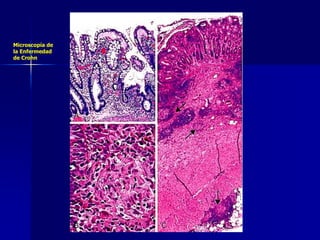

Enf. de Crohn

Microscopía de

la Enfermedad

de Crohn